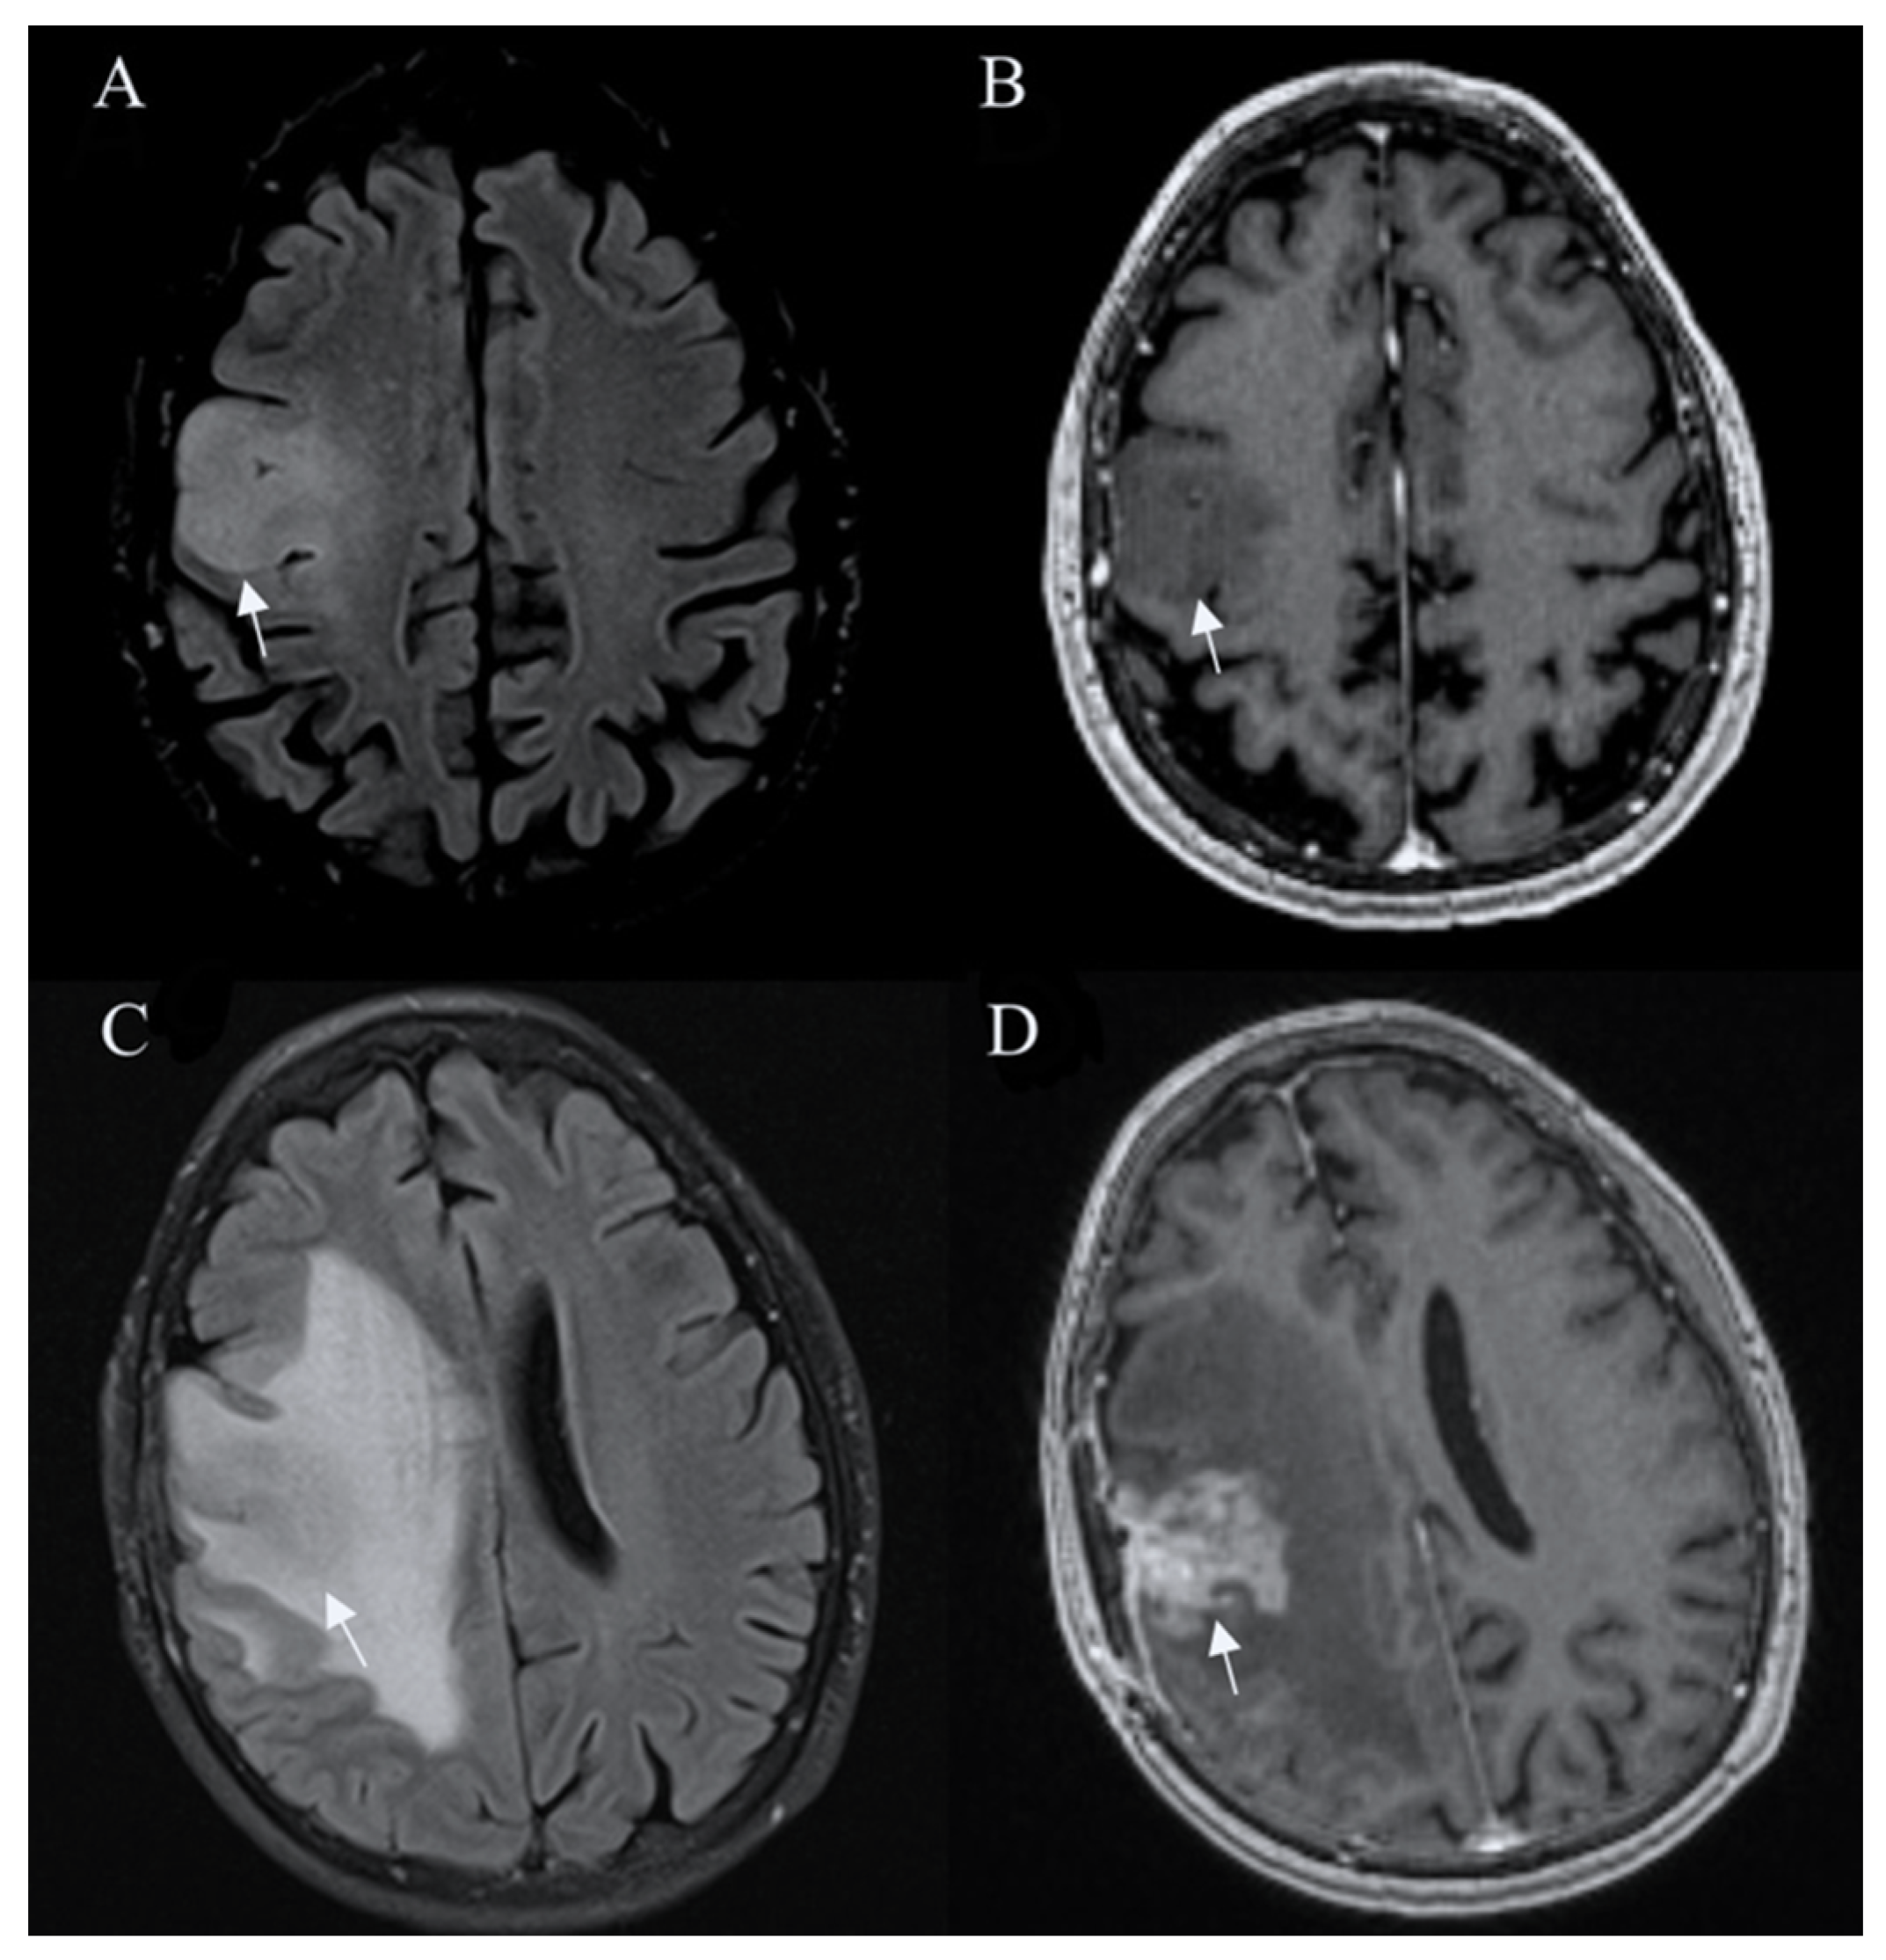

Standard Imaging Sequences

- Broen, M.P.G.; Smits, M.; Wijnenga, M.M.J.; Dubbink, H.J.; Anten, M.H.M.E.; Schijns, O.E.M.G.; Beckervordersandforth, J.; Postma, A.A.; van den Bent, M.J. The T2-FLAIR mismatch sign as an imaging marker for non-enhancing IDH-mutant, 1p/19q-intact lower-grade glioma: A validation study. Neuro-Oncology 2018, 20, 1393–1399. [Google Scholar] [CrossRef]